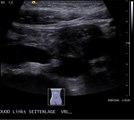

Erweitertes Duodenum mit Zieharmonikafalten

Erweiterter Angangsteil des Zwölffingerdarms (Duodenums) bei Kompression dieses Darmabschnittes durch die darüberliegende obere Darmarterie (Arteria mesenterica superior). Dadurch behinderter Nahrungstransport (Wilkie-Syndrom, Arteria mesenterica superior-Syndrom, AMS)